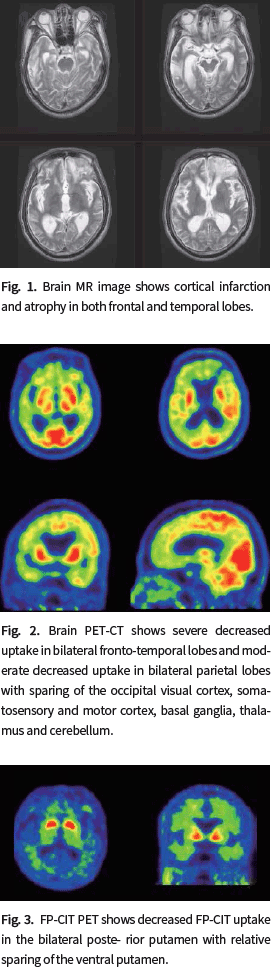

진단기준을 충족하고 있다. 또한 MRI에서 양측 전두엽과 측두엽에 경색 외에 대뇌 위축 소견이 관찰되고

있으며 F-18 FDG PET에서 일부를 제외한 대뇌 피질 전반에 대사가 매우 감소되어 있어 전두측두엽치매를

강하게 의심해 볼 수 있다.